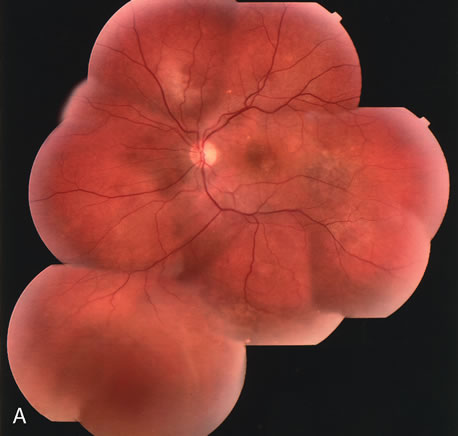

Fig. 14. A. Color photograph of the right eye shows a ramified pattern of choroidal vascular abnormality irradiating from the peripapillary area toward the macula. The dilated vascular channels end with bulging polyp-like structures. A larger, orange, saccular dilation is seen inferior to the macula (white arrow); leakage of fluid from this vascular abnormality results in serosanguineous pigment epithelium detachment (black arrows). B. The corresponding fluorescein angiogram composite highlights the vascular lesion in the peripapillary area and the serosanguineous detachment of the pigment epithelium that extends inferiorly and temporally off the macula.